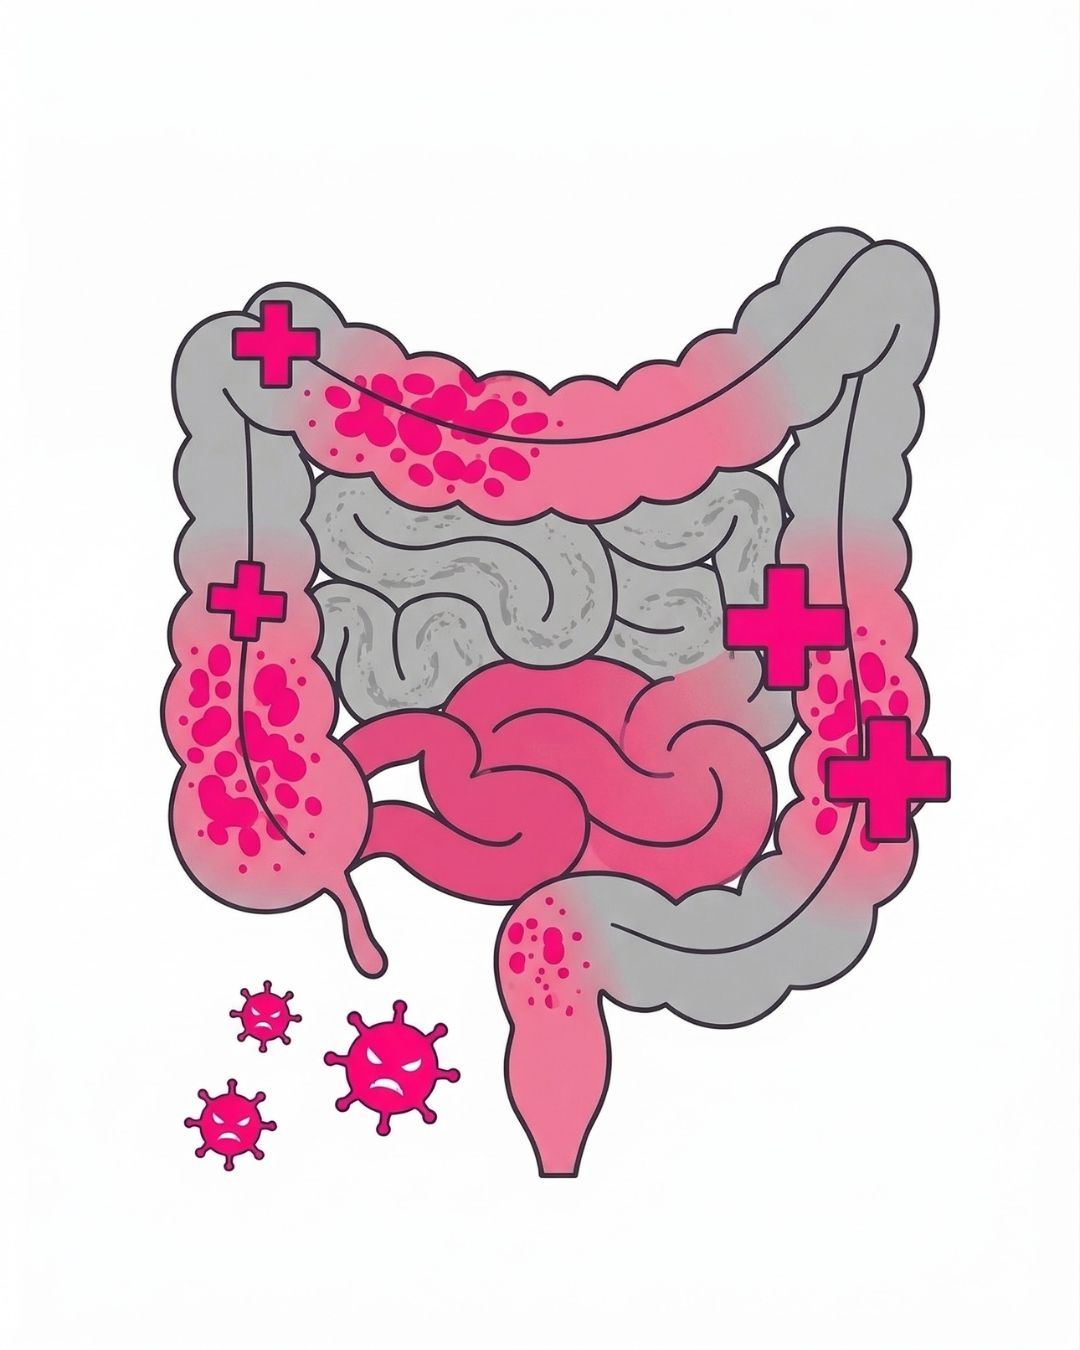

Darmklachten verhelpen?

Herstel je rust met een orthomoleculaire aanpak

Loop je dagelijks rond met een opgeblazen buik, onregelmatige stoelgang of vermoeidheid? Ontdek hoe we met persoonlijk voedingsadvies de werkelijke oorzaak van jouw darmproblemen aanpakken voor een blijvend resultaat.